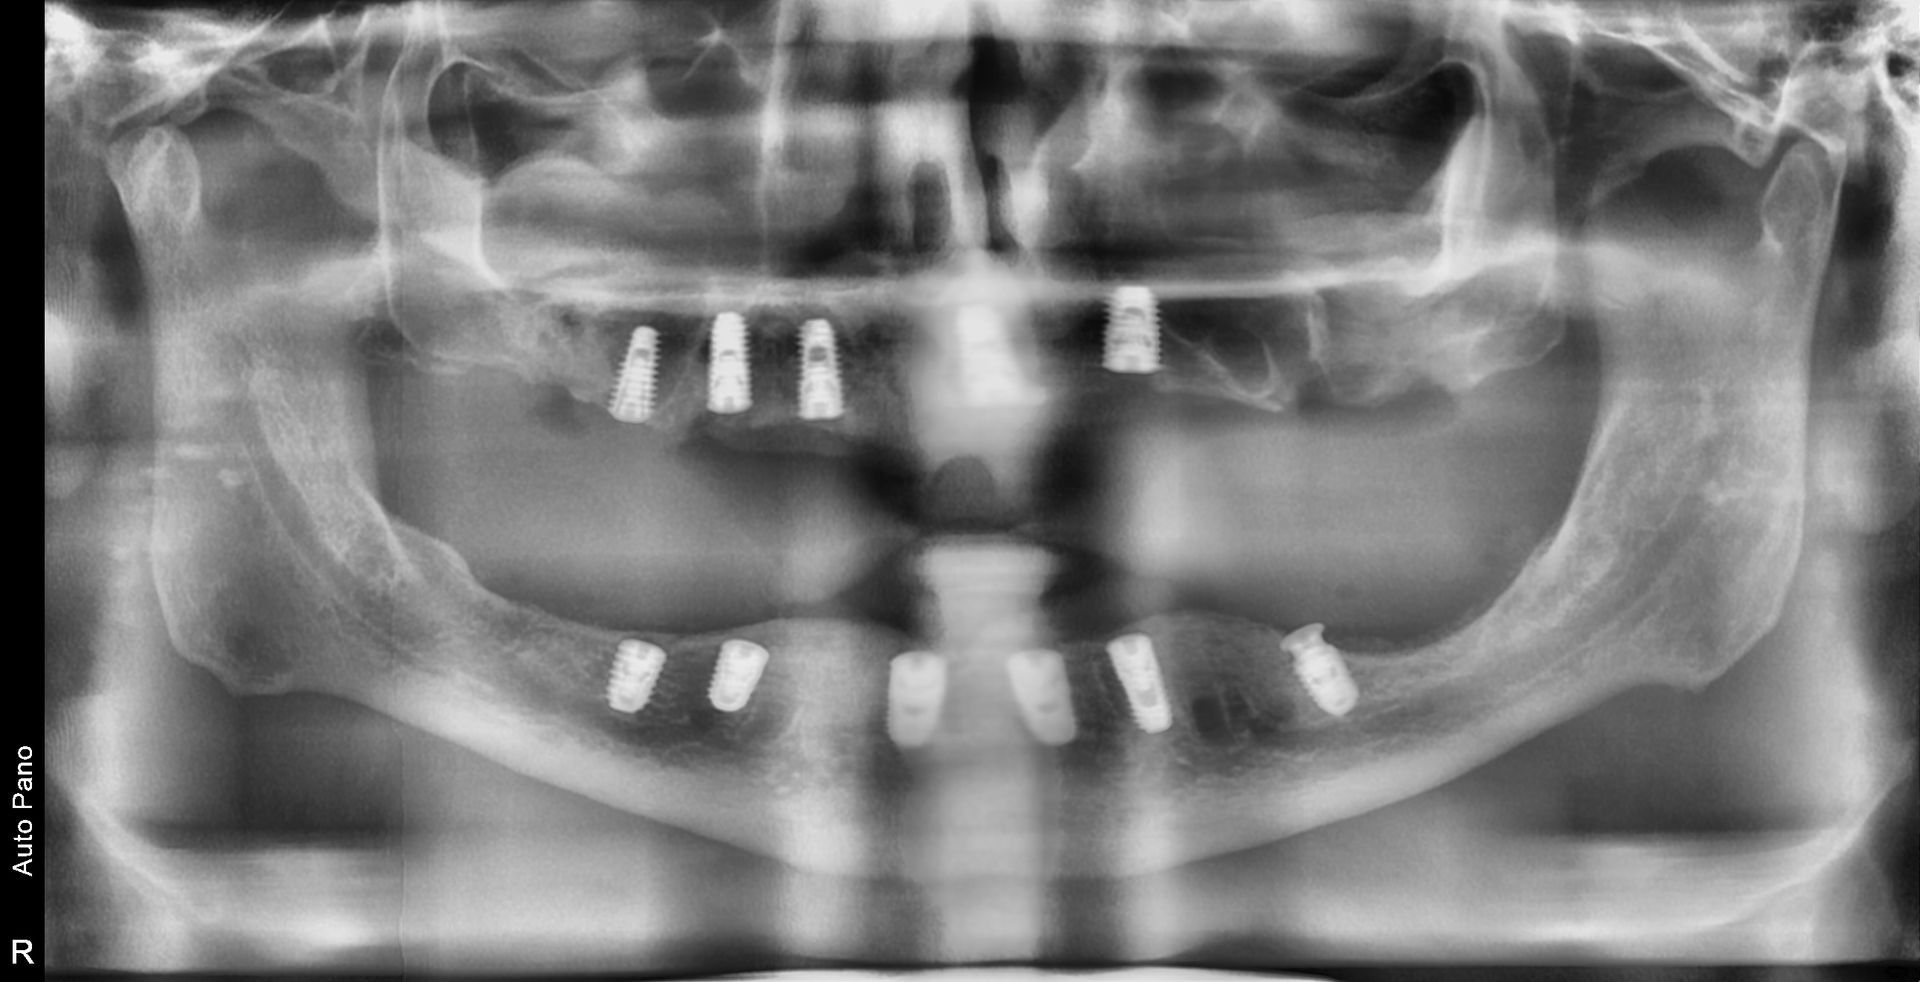

This image shows the implants placed in the planned positions on both the right and left sides of the mandible.

Although the mandibular bone is denser than the maxillary bone, many areas lie close to the nerve canal, making careful selection of implant angulation and length essential.

Immediately after surgery, a temporary denture is used to maintain function and speech.

The inner surface of the denture is adjusted so that it does not put pressure

on the surgical sites, allowing the patient to minimize discomfort while maintaining appearance.